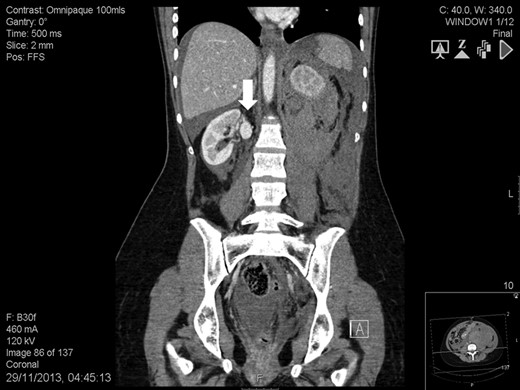

The patient was placed in left lateral decubitus. An 8-cm-long suprapubic incision extended to the right iliac fossa was performed and the retroperitoneum was entered. A hand-port (GelPort® Laparoscopic System, Applied Medical, USA) and three 12-mm ports, one for the 30° camera and the others for the instruments were inserted. Ureter, renal artery and renal vein were divided. The kidney was extracted through the incision, flushed and immerged into a cold solution (Soltran, Baxter Healthcare, USA). The aneurysm was resected and the remaining two arteries were prepared for implantation (Fig 3). The patient was placed supine and the hand-port access was used for the autotransplant. The renal vein was anastomosed to the external iliac vein whereas the renal arteries were anastomosed to the external iliac artery. The ureteral-vesical anastomosis was performed according to Lich-Gregoire. The procedure took 481 min. Extraction, cold ischaemia and anastomosis times were 2, 48 and 52 min, respectively. Intra-operative blood loss was 280 mL. The postoperative course was uneventful. Histology showed myxoid medial degeneration of the renal artery. Three years later, her serum creatinine is 79 mmol/L with no RAA recurrence. She also completed two uncomplicated pregnancies.

Intra-operative finding: right saccular renal artery aneurysm (white arrow) involving the main arterial branch and extending to the level of its distal bifurcation.